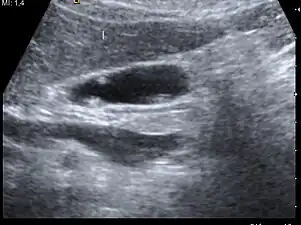

Diagnosis is typically by ultrasound or CT imaging.

Ultrasound image of gallbladder polyps measuring 3–7 mm.